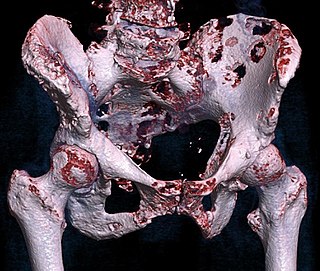

3D rendered CT of hip bone metastases.jpg

Top : non-cancerous bone tumor, bottom: cancerous bone tumor